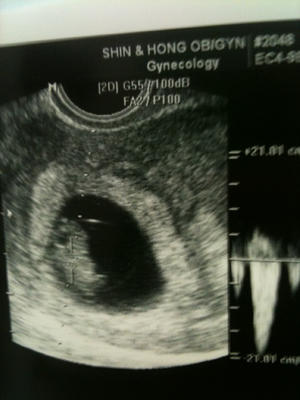

임지선 제공

임신 사실만 확인하고 도망치듯 산부인과를 뛰쳐나온 나흘 뒤, 정식으로 마음을 다잡고 회사 앞 산부인과를 찾았다. 그리고 보았다. 초음파 사진 속, 내 자궁벽에 비스듬히 등을 기댄 채 한쪽 다리를 하이킥하고 있는 ‘곤란이’의 모습을. 이어서 들었다. 쿵쾅쿵쾅 뛰어대는 아이의 심장 소리를. “이제 와서 어쩔 건데?” 아이는 우리 부부에게 이렇게 말하고 있었다.